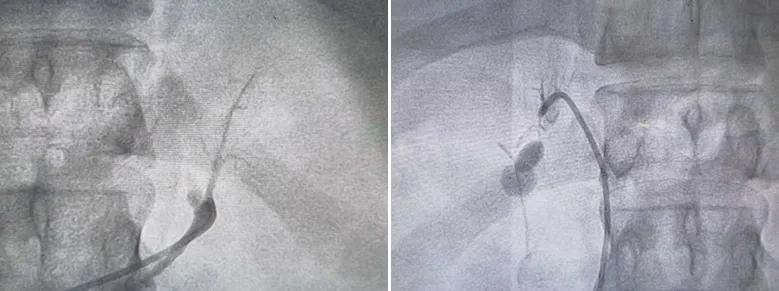

黄先生术前肾上腺静脉采血-左右肾上腺静脉

肾上腺动脉消融前

肾上腺动脉消融后